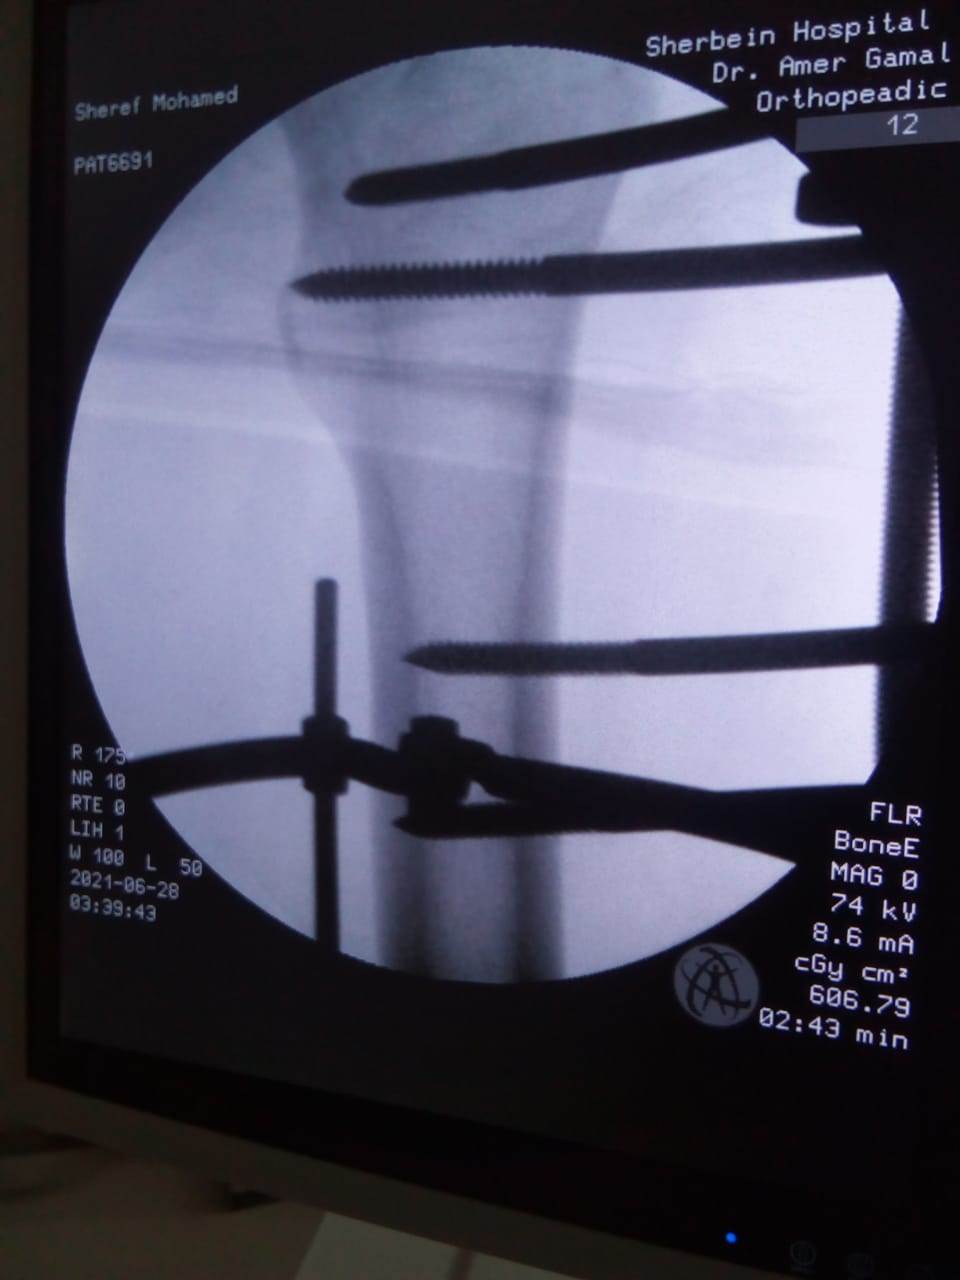

حيث تم إجراء تدخل جراحي دقيق لشاب يعاني من كسر مضاعف من الدرجة الثالثة، إثر طلق ناري، أدى إلى تهتك بالأنسجة، وكسور متفتتة بالفخذ، وذلك عن طريق جهاز "الليزاروف"، وتعد واحدة من عمليات العظام الكبرى والمتقدمة ذات المهارة الخاصة.